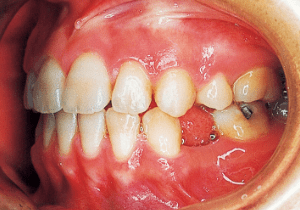

5 7-20-’87 After treatment

The treatment progressed more favorably than anticipated, with the open bite and Class II malocclusion nearly resolved within five months of treatment initiation. However, discontinuing the use of rubber bands often resulted in an open bite.